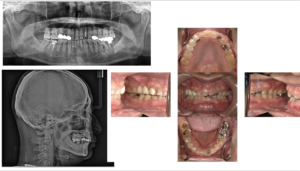

最近ではフルマウスの噛み合わせを0から作りスマイルの改善を行うケースが増えてきています

初診時

フェイススキャンにてスマイルの検討、顎骨の位置より現実治療可能範囲で設定

1回目の仮歯におけるスマイルの変化

細かいところは歯周組織の維持、根管治療のやり直し等ありますが細部も顔貌もできるだけ整うように工夫しながら治療しております。

顎関節も含めて難しい治療ですが悩まれている患者さんいれば相談対応いたします。